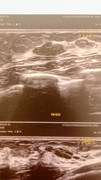

Salve egregio Dr Catania, sono una ragazza di 30 anni, spero tanto che possa rispondermi. Sono molto preoccupata in merito ad una formazione ovalare ipoecogena che mi è stata riscontrata a febbraio del 2022, la cui misura era di 13.6 mm. A detta dei radiologi e senologo la lesione è compatibile con un fibroadenoma, solo che dall'ultimo controllo fatto a distanza di un anno, c'è stato un lieve incremento di 2 mm e mezzo. Vorrei sapere se occorresse fare un'ulteriore indagine o semplicemente l'ecografia mammaria come di routine. Nell'attesa di un riscontro, le mostro la foto e la ringrazio anticipatamente 🩷🙏🏼

Ciao Nika, secondo me, se il nodulo ha caratteristiche benigne, una crescita di 2 mm mi sembra davvero minima, a volte dipende anche dalla prospettiva in cui è stata fatta l’eco.

A me è capitato di fare 2 eco a distanza di pochi giorni e avere una minima differenza di misura. Spero di non sbagliarmi il dottore, saprà dirti più

Stia assolutamente tranquilla.

1) Malgrado il fibroadenoma sia una lesione che può incrementare il suo volume in modo significativo e rapidamente

2) le probabilità di una degenerazione neoplastica sono trascurabili.